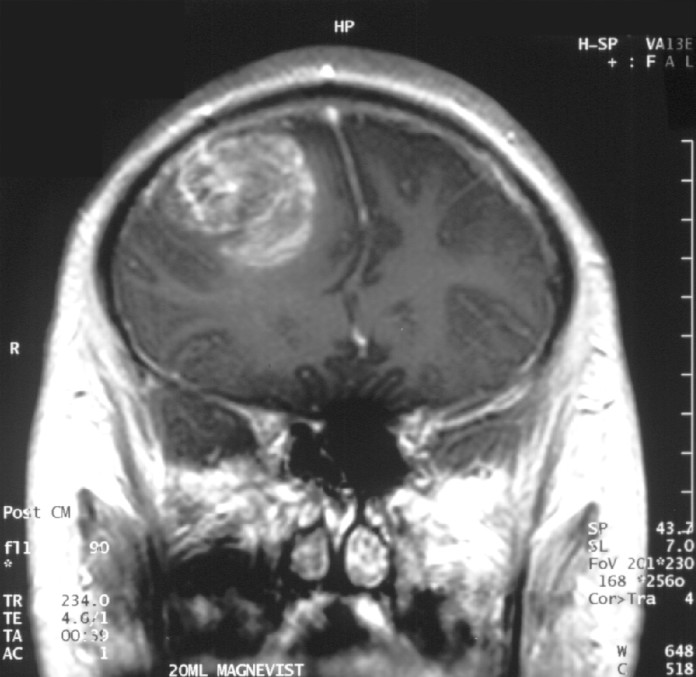

tratamiento de radio terapia y quimioterapia en tumor cerebral, Tumor cerebral grande